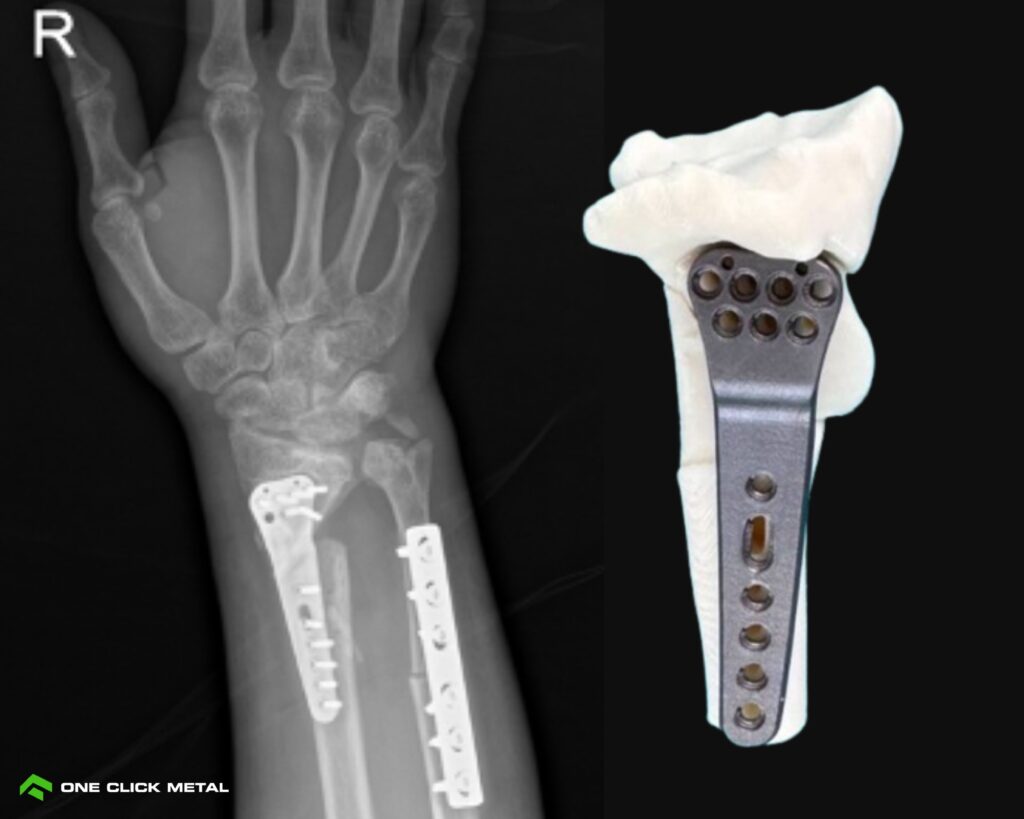

Lerdsin Hospital, a leading public teaching hospital in Bangkok, Thailand, is transforming orthopedic care through the use of patient-specific metal 3D printed implants. By integrating metal additive manufacturing directly into

lerdsin case study mockup

Case Study

Lerdsin hospital

Transforming orthopaedic care with patient-specific metal 3d printed implants.